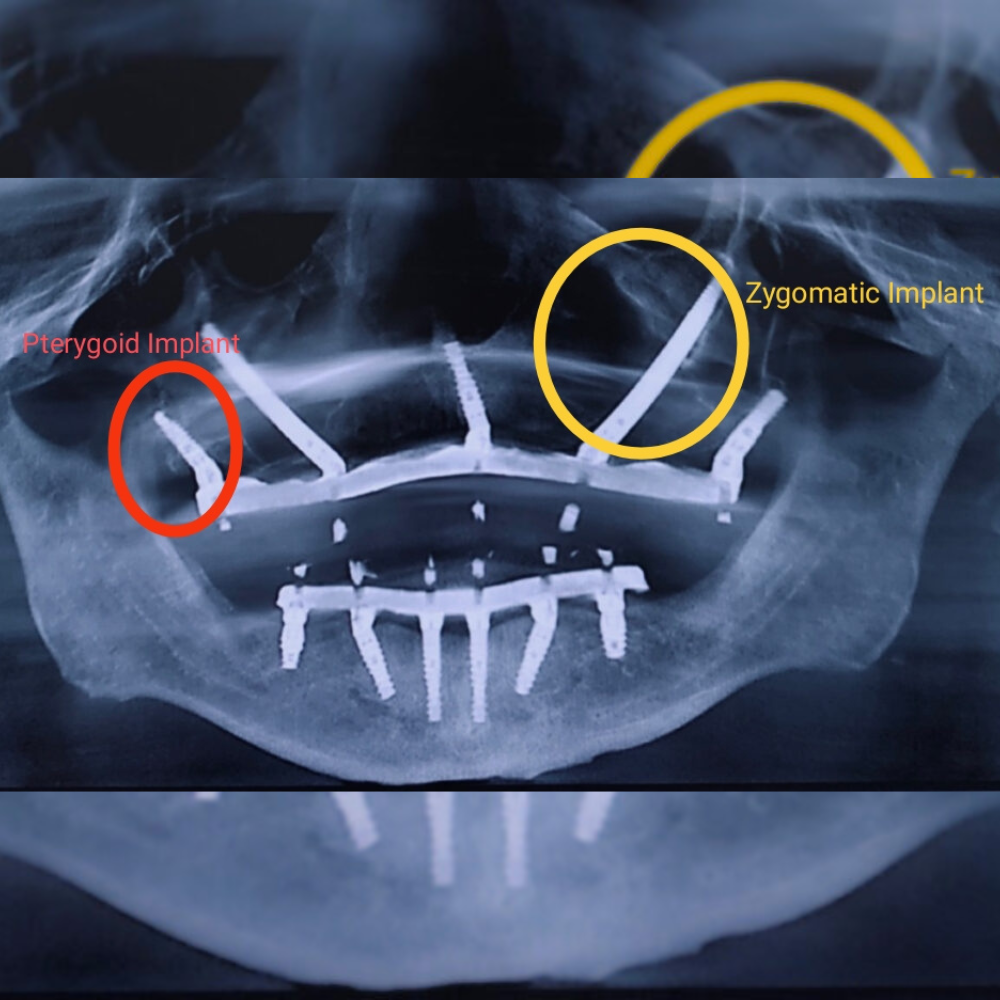

Zygomatic and Pterygoid Implants

We offer advanced zygomatic and pterygoid implants for patients with severe bone loss. These specialised implants provide strong support for fixed teeth without bone grafting, restoring smiles and confidence.